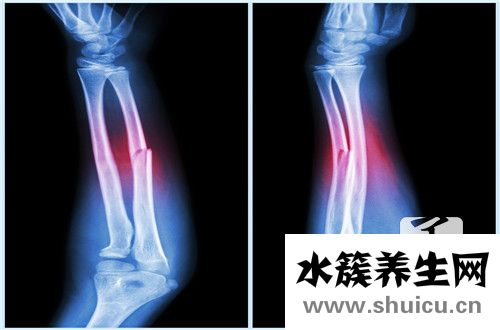

提起骨折,相信大家都比較熟悉,骨折也是屬于疾病的一種,主要癥狀就是骨頭斷裂,這種疾病會直接影響到患者的行動能力,同時還伴有非常劇烈的疼痛感,比如左肱骨骨折,這種情況千萬不要延誤治療的最佳時期,不然...